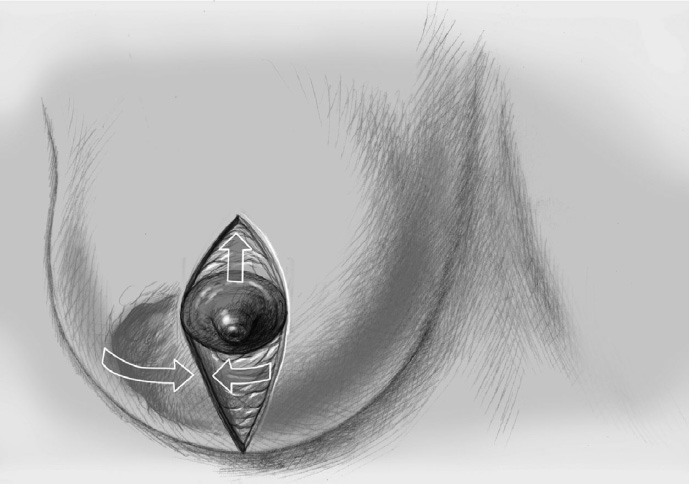

The adjacent parenchyma is mobilized subcutaneously so that the defect can be filled with lobes of breast tissue. Mobilization means exposing the breast relative to the skin or muscle to achieve adequate mobility of < 25% or > 25% as required.

Tension-free approximation for complete intramammary cover of the defect

To cover the defect, the glandular lobes are mobilized from the adjacent parenchyma after subcutaneous dissection. The principle of intramammary lobe creation is to mobilize large parts of the breast (> 25%) either relative to the skin or relative to the pectoralis muscle. This “liberation” of the breast from one of its two planes of fixation allows adequate dissection and rotation of sufficient breast tissue. The Y-flap and rotation flap shown in Chapter 3.2.1 are examples of intramammary dissection.

When the breast is mobilized subcutaneously, it must be ensured that both the dissected skin layer and the breast tissue are sufficiently thick. For the layer of breast tissue, a minimum thickness of 1 cm is desirable. The ratio of base to length must also be considered.

The mobilized breast lobes are rotated into the defect and approximated by interrupted sutures. Complete covering of the defect is desirable.